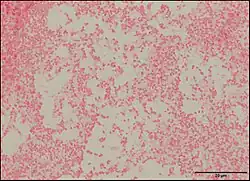

P. vulneris has a rod-like (bacilli) shape, and it achieves motility using peritrichous flagella (covering the whole body of the bacteria). P. vulneris is facultatively anaerobic, and is not spore-forming. Optimal growth occurs at 35-37 °C, and it can colonize on a simple nutrient medium. Colonies are generally smooth and low convex with shiny surfaces.[3]